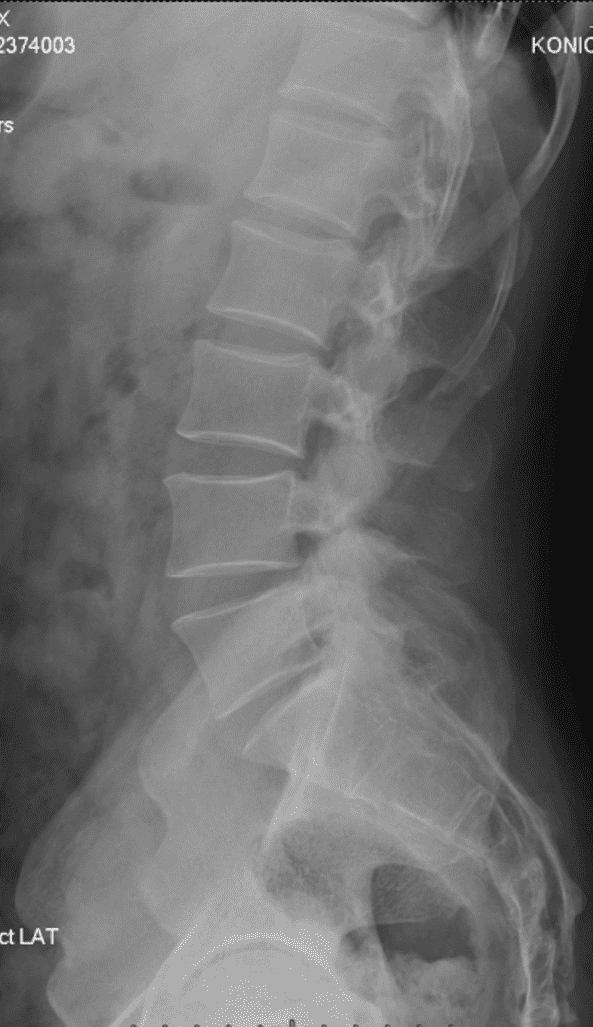

椎骨 / 髂骨 精确标记例

将传统通过点标记训练的 UNet 峰值 22 通道分类模型 + UNet ROI 窗口粗分割模型 替换为对线性顺序和先验顺序更精确的 HRNet 模型,识别率提高并且对于复杂情况的识别能力大幅提升。

将 UNet 训练的髂脊线识别模型(UNet 只适合进行分割,对于线段识别定位预测为概率热图,并不方便进行线段化)替换为 VGG16-BN 专注于线段提取。